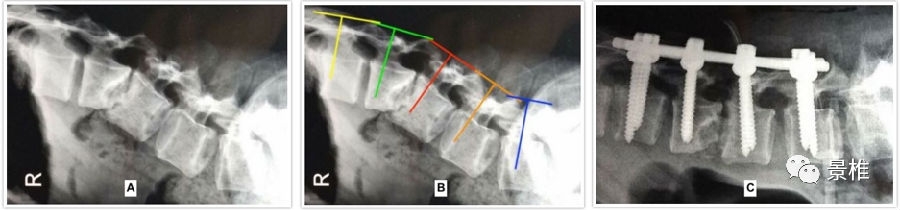

脊柱有生理弯曲,每一个椎体的置钉头尾倾角度都不一样。

尤其碰到骨折、畸形、生理曲度有较大高低起伏变化的,每个椎体的头尾倾角度完全不同。

已有学者总结出经验:胸腰椎椎弓根置钉的头尾倾角度,与上下相邻关节突关节所在的平面垂直。

有时术中判断出垂直于上下两个关节突关节的所在平面也有些困难。

君子性非异,善假于物焉。此时利用直角器械,比如甲状腺拉钩、事先折好角度的克氏针等等:短头贴在相邻两个关节突上,那长杆的指向就是钉道的走行。